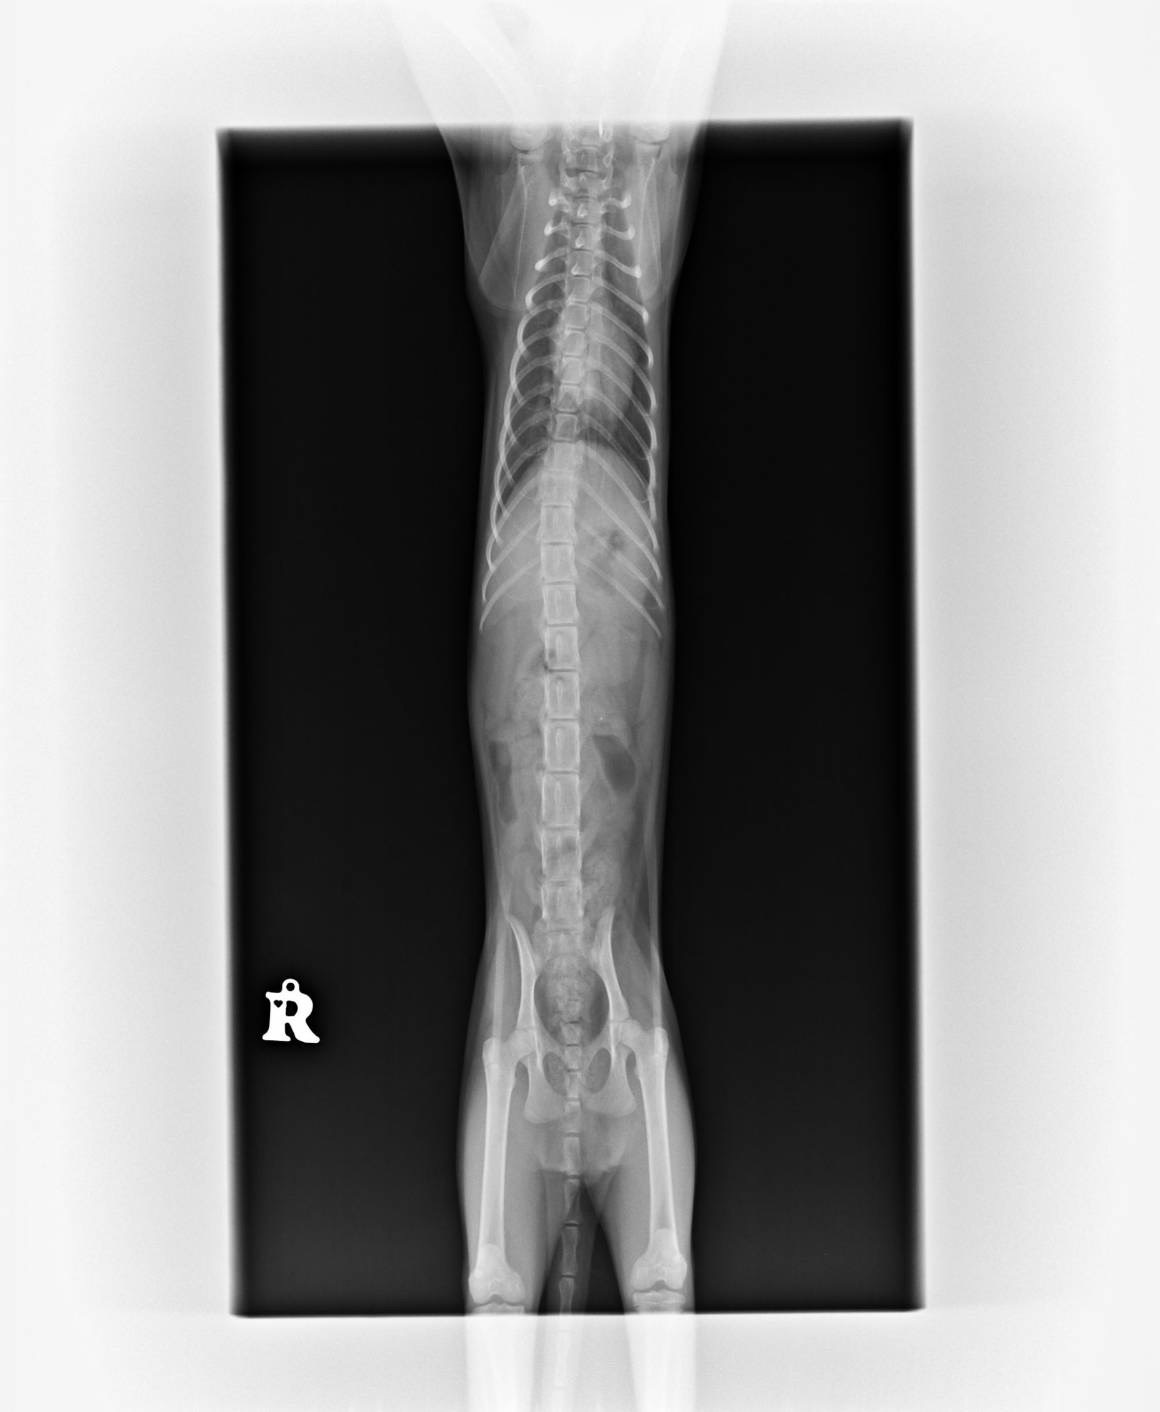

以下為皮皮在不同時間點接受的醫療紀錄、買賣契約書、X光影像、病毒檢驗與血液報告,呈現完整醫療照護歷程與佐證。

▲ 皮皮的X光正面影像,檢查是否有脊椎異常或其他神經壓迫。